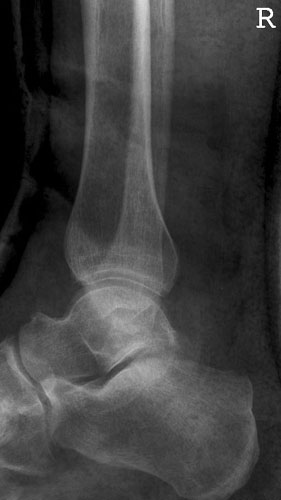

OSG a.p.

129_5.jpg

Fehler

Außenrotation bzw ungenügende Rotation des Fußes nach innen. Der mediale Gelenkspalt projiziert sich besonders schön frei, hingegegen ist der laterale Spalt verschattet.

Abhilfe

Fuß weiter nach innen drehen lassen, bis beide Malleolen auf einer Höhe parallel zum Film stehen.